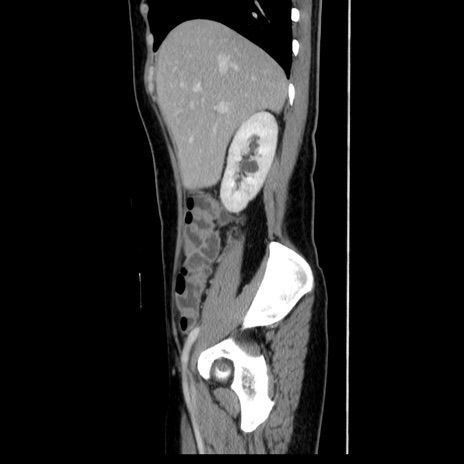

症例39(矢状断像)

【症例】40歳代女性

【主訴】上下腹部痛

【現病歴】2日目から下腹部痛あり。夜間は痛みで眠れなかった。昨日より上腹部痛と下痢が出現。臥位で痛みは軽快したため、休んでいた。本日になって臥位でも立位でも痛みが強くなってきたため救急要請。

【既往歴】子宮内膜症

【身体所見】部:平坦・軟、左上下腹部に圧痛あり、反跳痛あり。

【データ】WBC 21800、CRP 26.78

CT